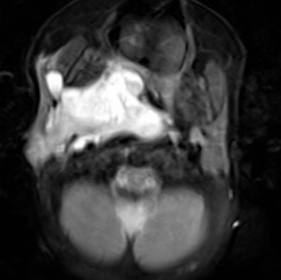

病例分享 | 聚桂醇泡沫硬化治疗腮腺术后面部血管畸形

病例分享 | 注射药物治疗肝血管瘤病例分享——鸡刀杀牛:以注射的微损伤达到痊愈的

囊肿性疾病聚桂醇硬化治疗四例